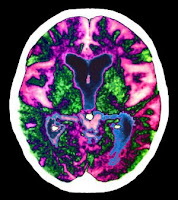

Segons publica la prestigiosa revista Science, un fàrmac ja conegut, el betaxoreno, podria ser efectiu per combatre l'Alzheimer, eliminant les proteïnes beta-amiloides del cervell. Almenys és el que suggereixen els assaigs duts a terme amb ratolins.

L'estudi, realitzat per Casi Western Reservi University (Ohio), assenyala que l'efecte és molt ràpid: en només 6 hores, després d'administrar el fàrmac, les masses d'aquestes proteïnes s'havien reduït un 25%. I l'efecte durava, almenys, tres dies.

Per demostrar que aquest efecte també podria ser beneficiós per combatre l'Alzheimer, es va provar en tres tipus de ratolins en els quals se'ls havia induït una malaltia similar a l'Alzheimer. El resultat és que els ratolins es feien més llestos: si eren incapaços de construir els seus nius, a les 72 hores començaven a manejar els materials (tires de paper) per fer-se un.